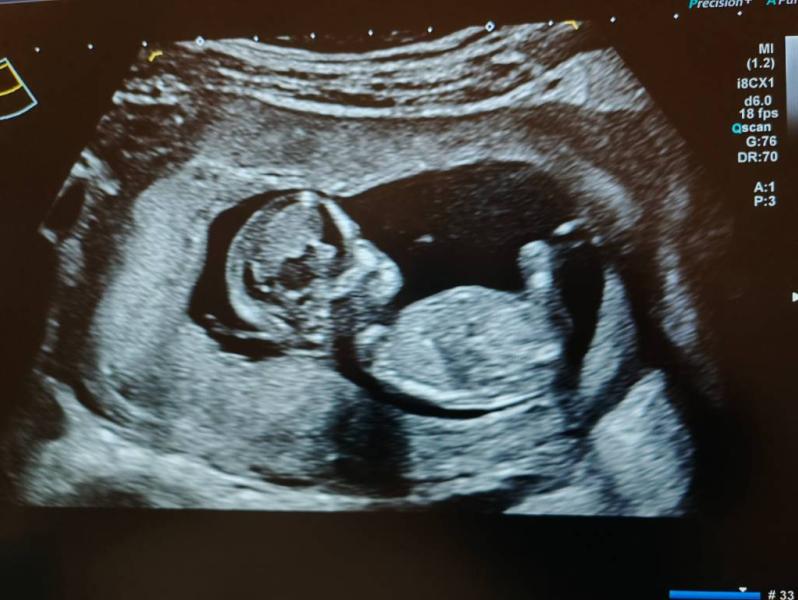

Девченочки привет) кто уже на опыте, у кого много деток, может у кого глаз алмаз 😄есть фото со скрининга может кто-то что-то увидит или попробует определить пол буду признательна😇🙏я совсем ничего не вижу, может поза не удачная, но все-же давайте попробуем 🥰🙈

Непонятно ) лучше кровь сдать на пол либо дождаться 16 недель и узнать пол

Чтоб разглядеть пол, нужно фото между ног. Что вы там с боку рассмотреть пытаетесь?😂